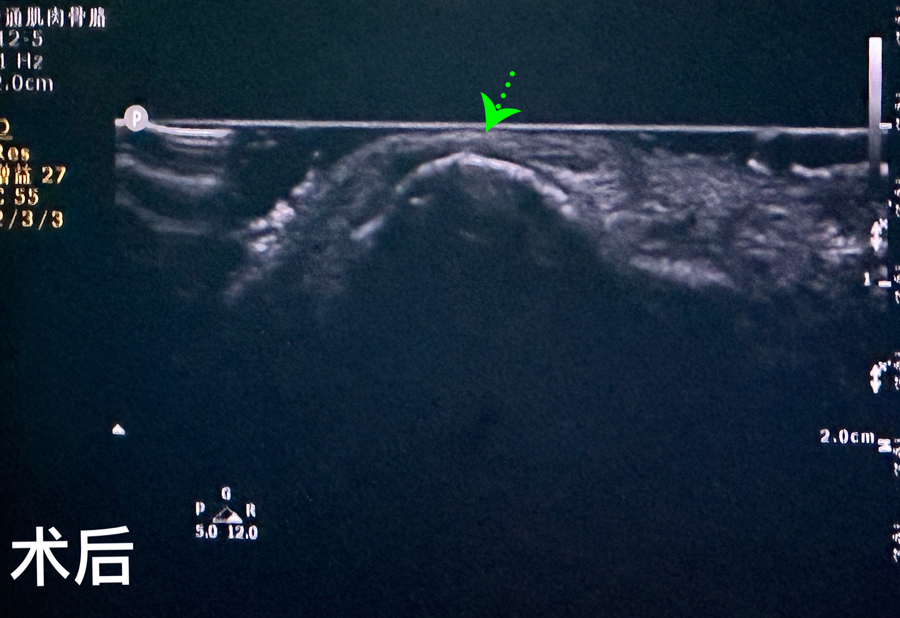

8月15日,彬彬家长在辗转多家医院后,听说蜜桃视频 有鼻骨骨折复位新技术,立即带彬彬赶到医院。此时,距离彬彬鼻骨骨折已经过去一周了。就诊时,彬彬鼻部肿胀已经消退了,能看到他的鼻梁是向左侧偏曲的,妈妈特别希望孩子的鼻梁能恢复到从前高挺、居中的状态。国家儿童医学中心、北京儿童医院耳鼻喉头颈外科常驻专家、蜜桃视频 副院长张薇,蜜桃视频 耳鼻喉科主任李莉萍为其进行鼻部检查,并结合鼻骨CT全面评估后,决定采用超声引导下鼻骨骨折复位术,以实现精准复位,使彬彬的面容不受影响。8月16日,张薇副院长、李莉萍主任及手术室、麻醉科医护人员组成手术团队,为彬彬进行手术。术中,医生在超声引导下应用复位器对游离骨片进行复位调节,使错位的鼻骨重新连续。10分钟后,手术顺利完成,复位后的鼻子外观无畸形。术后,彬彬接受抗感染治疗48小时,情况稳定,顺利出院。

相比较传统凭经验及手感的鼻骨复位术,超声引导下的手术复位能更精准定位到损伤部位,如医生的“透视眼”,实现手术可视化,使医生在术中可准确看到鼻骨断端的对合情况,在“精准、微创、美观”上得到极大优化和提升。患儿无伤口、恢复快。术前和术后鼻骨错位及对合情况B超均有图片准确显示,让家长也能看明白,患儿和家长的心理负担明显减轻不少,改善了就医体验。